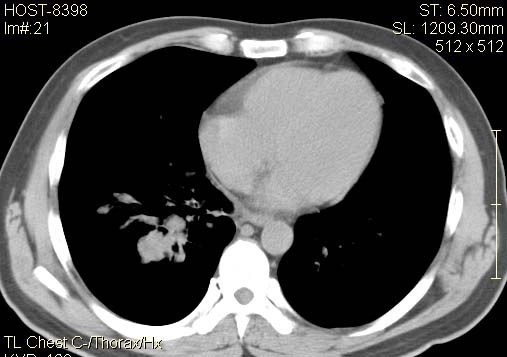

以下是引用qc80012345在2007-4-17 12:33:00的发言:[br]右肺下叶周围型肺癌伴肺门及纵隔内淋巴结转移;比较清楚。

以下是引用qingyuan在2007-4-17 14:19:00的发言:[br]右肺下叶外侧后段胸膜下区节结样病变、分叶、内可见空洞,壁厚薄不均,胸膜凹陷、肺门周围区纹理增粗、僵硬、并近似小结节样改变,肺门区软组织节结、纵膈淋巴结肿大,患者病史长、抗炎治疗无好转炎性改变基本排除,考虑:右肺下叶周围型肺癌伴纵膈及右肺门区淋巴结转移、肺内淋巴管受侵。